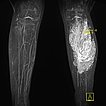

Coronal T1-weighted non-enhanced MRI shows an intramuscular, vascular lesion (isointense to the muscle) with marked interstitial hyperintense adipose tissue. This fatty tissue is more pronounced than would be usual in a normal venous malformation.

Axial T2-weighted MRI of the left lower leg shows multiple dilated, dysplastic veins in a venous malformation throughout the superficial flexor muscles. Slow flow causes stasis of the blood within the malformation with the formation of fluid-fluid levels. Almost the entire muscle consists of malformation and fatty tissue. Also visible is a large thrombus in a dilated, dysplastic vein.